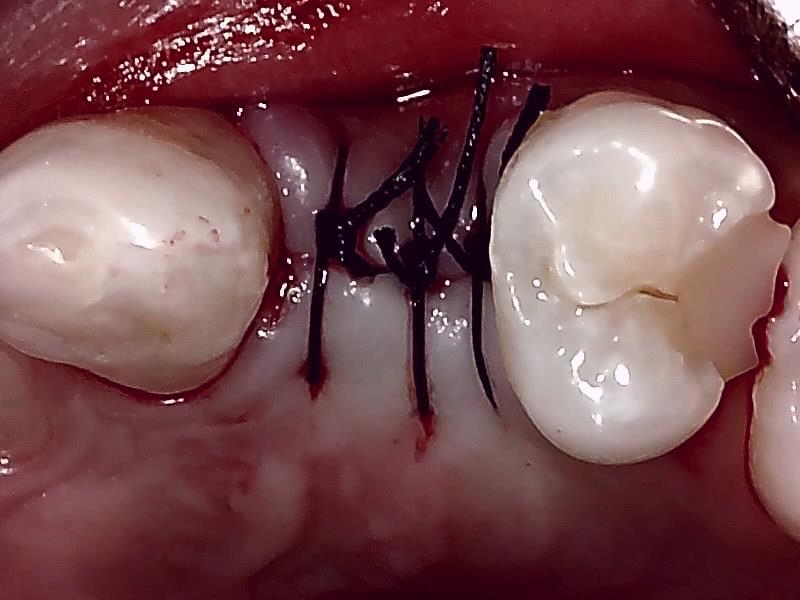

縫合

骨造成 自家骨移植

骨造成